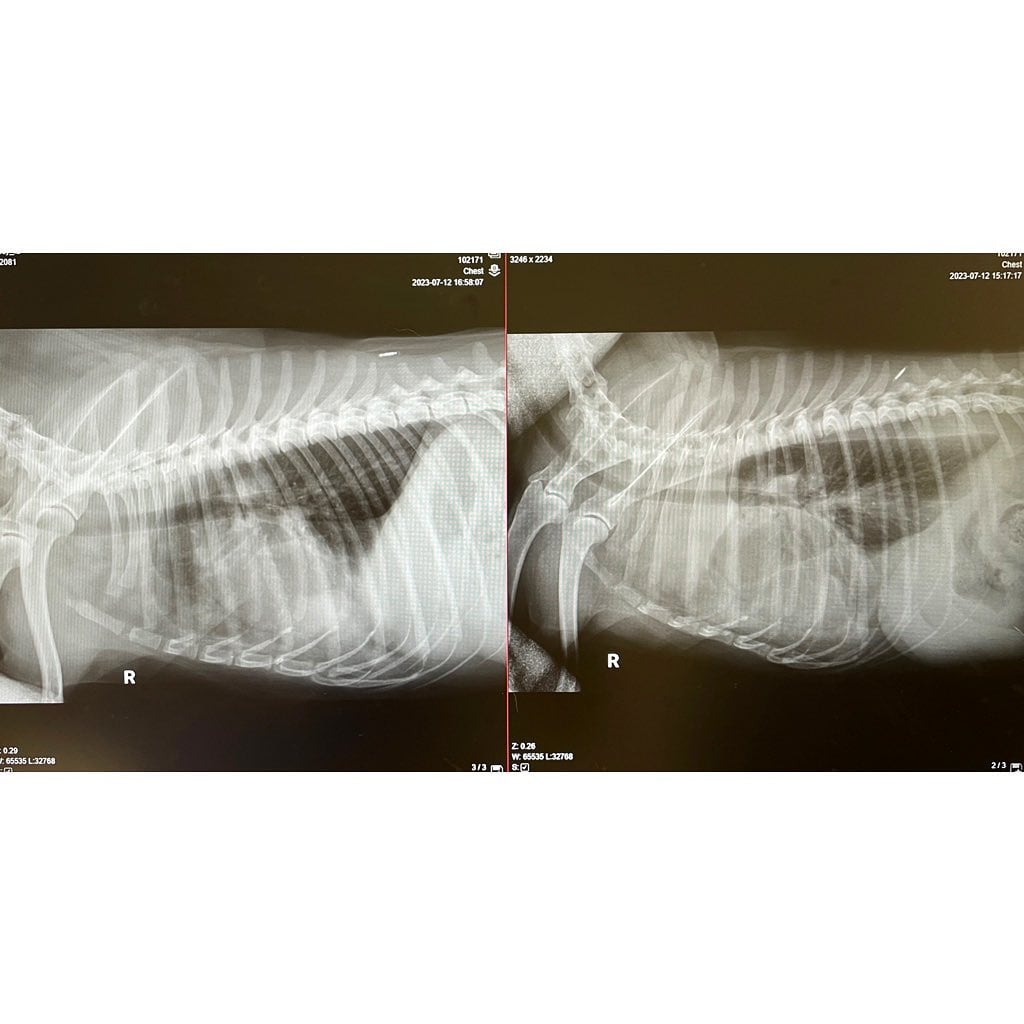

Cheems “fue a la clínica de nuevo el miércoles pasado, se drenaron 640 ml de sangre de la pleura de nuevo”.

“Debido a que el tumor crece entre la pleura y los pulmones, [el veterinario] explicó que es muy difícil extraer tejido para la prueba del tubo, pero por los síntomas y las imágenes pensó que sí. es muy probable que sea cáncer”.

También, se puede ver una foto de las radiografías después de que se extrajo el líquido de sus pulmones.